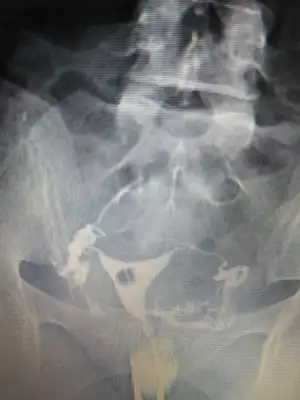

Onun hatlar karışık biraz. Çekim sonrası radyologun mesai saati bittiği için rapor yetişmemiş. Pazartesi alacak sonucunu. Kendi doktoru tüplerden birinde tıkanıklık var gibi konuşmuş ama başka doktorlara da göstermiş, basınçla açılmış demişler